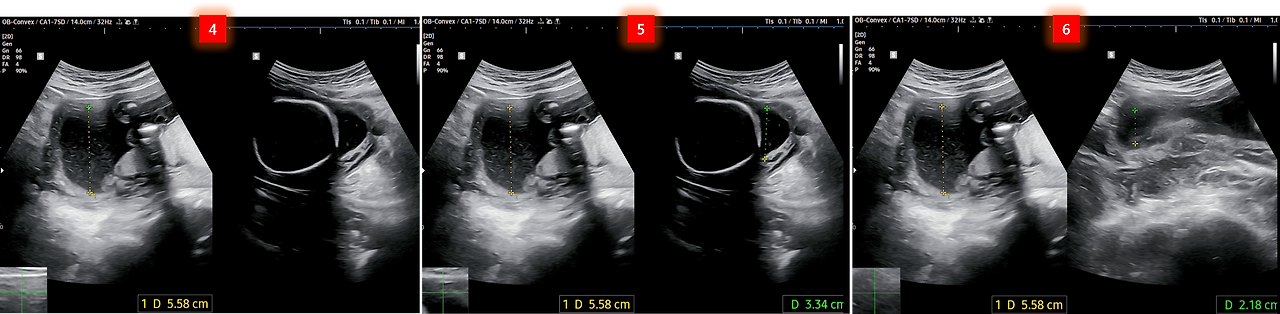

4~6. 양수량 검사를 한 것 같은데 지난번과 좀 다르네요.

지난번에는 4곳의 길이를 측정했는데 이번에는 3곳에서만 측정한 것 같습니다.

그때는 Q1~Q4의 값이 합쳐져 마지막 Q4 측정 시 AFI(양수지수) 값으로 나타났었는데 이번에는 그런 값이 안 보이네요. 여하튼 제 나름대로 초음파 사진에서 나온 각 깊이를 합쳐보니 11.1㎝로 나옵니다.

병원에서는 10㎝로 설명했다고 하니 제가 측정한 값은 맞지 않는 걸로...